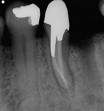

Treatment Examples

Surgical Endodontic Treatment

Hemisection with Cast Post and Core

All Treatment performed by Dr. Brian A. Christopherson